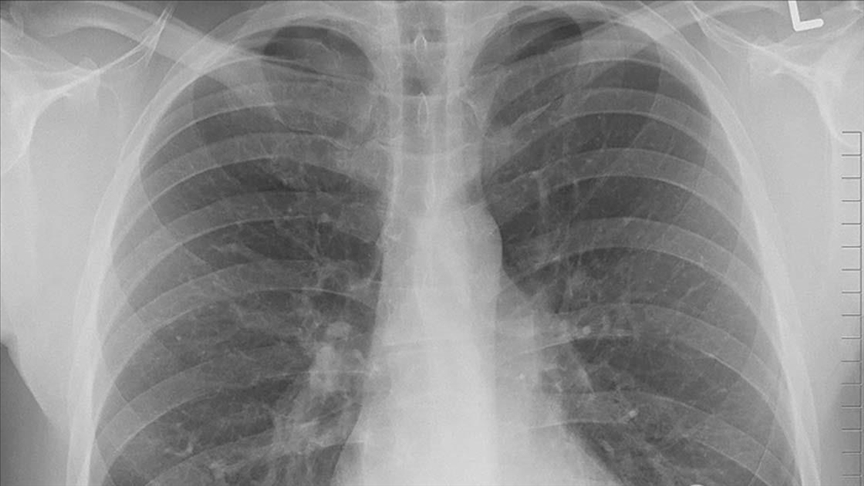

Yangın dumanına maruz kalmak sağlığı etkiliyor

Ülke genelinde meydana gelen orman yangınları sonrası oluşan dumanın insan sağlığı üzerindeki etkilerini en aza indirmek için alınması gereken önlemler paylaşıldı.

Yapılan bilgilendirmede, yangın dumanının göz, burun, boğaz ve akciğerlerde tahrişe yol açabileceği, öksürük ve hırıltılı nefes almayı zorlaştırabileceği belirtildi. Bu süreçte sağlığı korumanın en etkili yolunun, dumanlı havada kapalı alanlarda kalmak ve dışarıda geçirilen zamanı sınırlandırmak olduğu vurgulandı.

Açıklamada, özellikle kalp veya akciğer hastalığı gibi kronik rahatsızlığı bulunan vatandaşların dumanlı havaya maruz kalmasının ciddi sağlık sorunlarına yol açabileceği uyarısı yapıldı. Bu adımın, yüksek risk grubundaki kişiler için hayati önem taşıdığının altı çizildi.